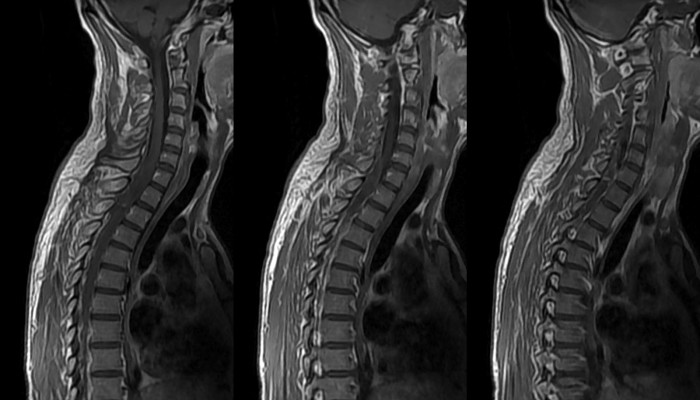

Диагноз спондилолистеза достаточно сложно установить без дополнительного исследования. Даже клиническая дифференцировка схожих состояний не дает однозначного ответа, предоставляя врачу несколько вариантов. Чтобы окончательно определиться с заключением, необходимо воспользоваться такими методами:

- Рентгенография позвоночника в нескольких проекциях.

- Магнитно-резонансная томография.

- Миелограмма.

- Электромиография.

Наибольшее значение имеют первые два исследования, однако томография предоставляет больше возможностей для диагностики. Последняя из указанных процедур используется с целью определения нервной проводимости. При подтверждении врачебного предположения о заболевании следует обязательно проконсультироваться у вертебролога и невролога для определения дальнейшей тактики лечения.